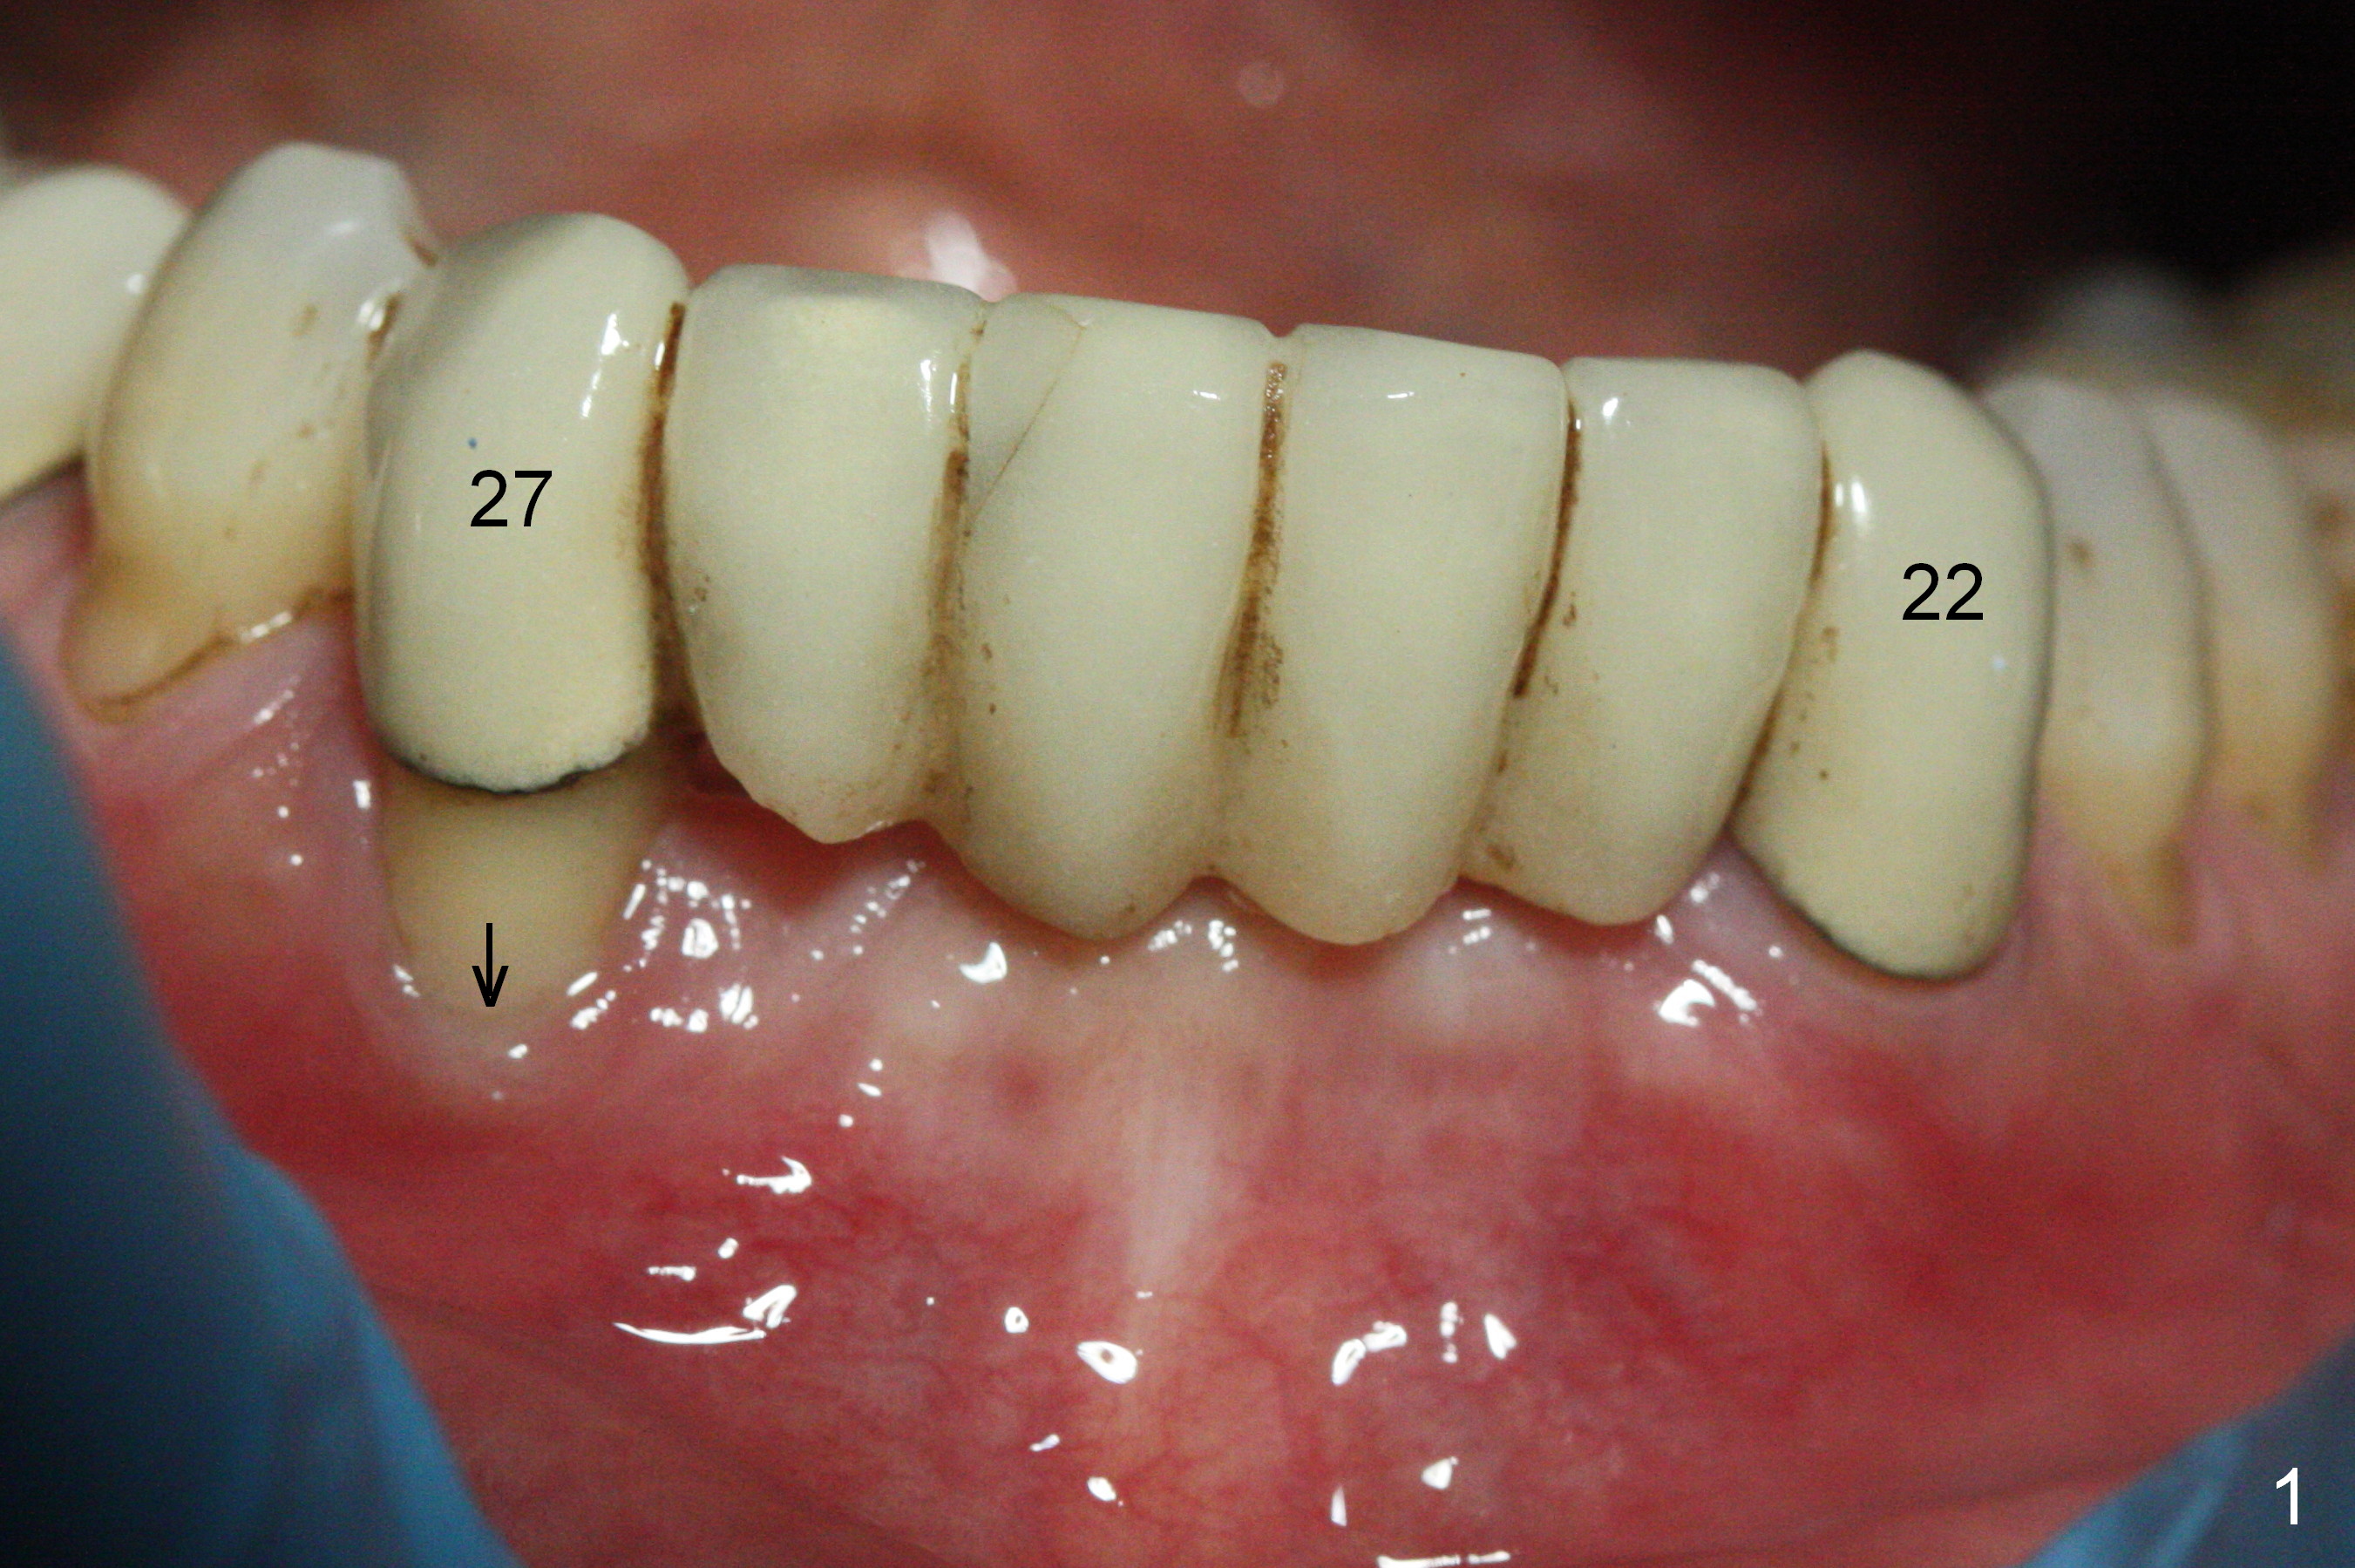

There is severe buccal gingival recession at #27 (Fig.1 arrow), as compared to that at #22. After removing the bridge and extraction of #27 (Fig.2 with severe loss of the buccal plate), a 3x18 mm drill is used to finish osteotomy (Fig.3). A 3.8x13 mm UF implant (Fig.3 green line) will be placed with 9 mm in the apparently solid, native (new) bone (blue line), while the coronal 5 mm will be occupied by the 5 mm cuff of a cemented abutment (pink line). The white dashed line is the gingival margin. The osteotomy is initiated as lingual as possible so that there will be at least 2 mm buccal gap when the narrow implant is placed. In spite of effort and precaution (guided surgery could control the trajetory), the coronal end of the implant tilts buccally so that a 4.5 mm 15 ° A 4 mm angled abutment is placed slightly subgingival (except buccal; Fig.5 A).

The mesial defect at #27 appears to have been repaired 8 months postop (Fig.8,9 *); there is no bone loss at 1-piece implant sites. The gingival recession seems to remain the same before and after removal of the provisional FPD (Fig.10,11). The bulging abutment at the cervix is less prominent when a straight abutment is used and prepared (Fig.12, 4.5x5.5(5) mm). There is no bone loss at #23, 25 and 27 sites 2.5 years post cementation (Fig.12-15), although the trajectory of the implants could be improved by using surgical guide (Fig.16-18).